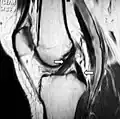

MRI shows normal signal of both cruciate ligaments (arrows) -